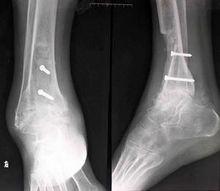

3、X線片上觀察骨折連線的情況,有無骨折不癒合、延遲癒合、畸形癒合,有無骨膜反應、游離死骨、骨硬化等情況。